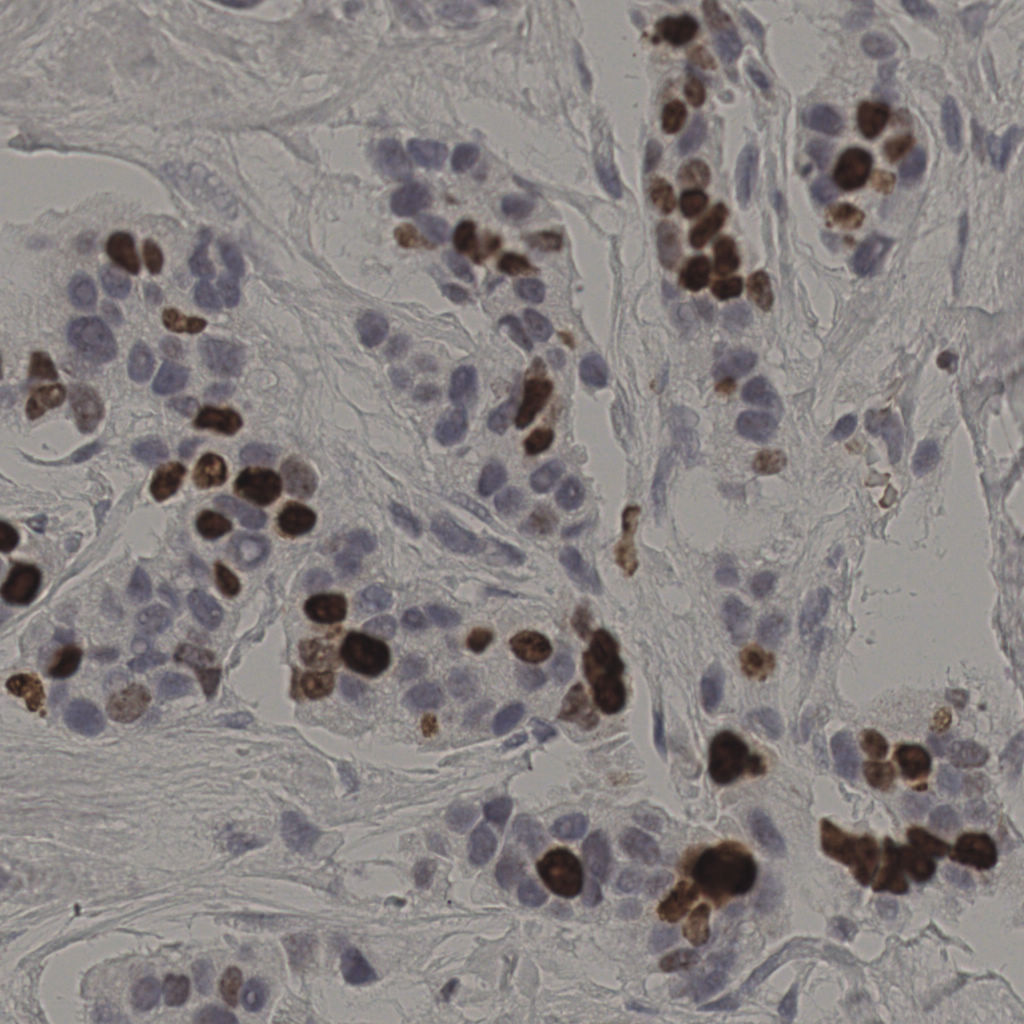

17.75%

Ki67 指数

阴 7986 阳 1723

20240285Ki-67.ndpi